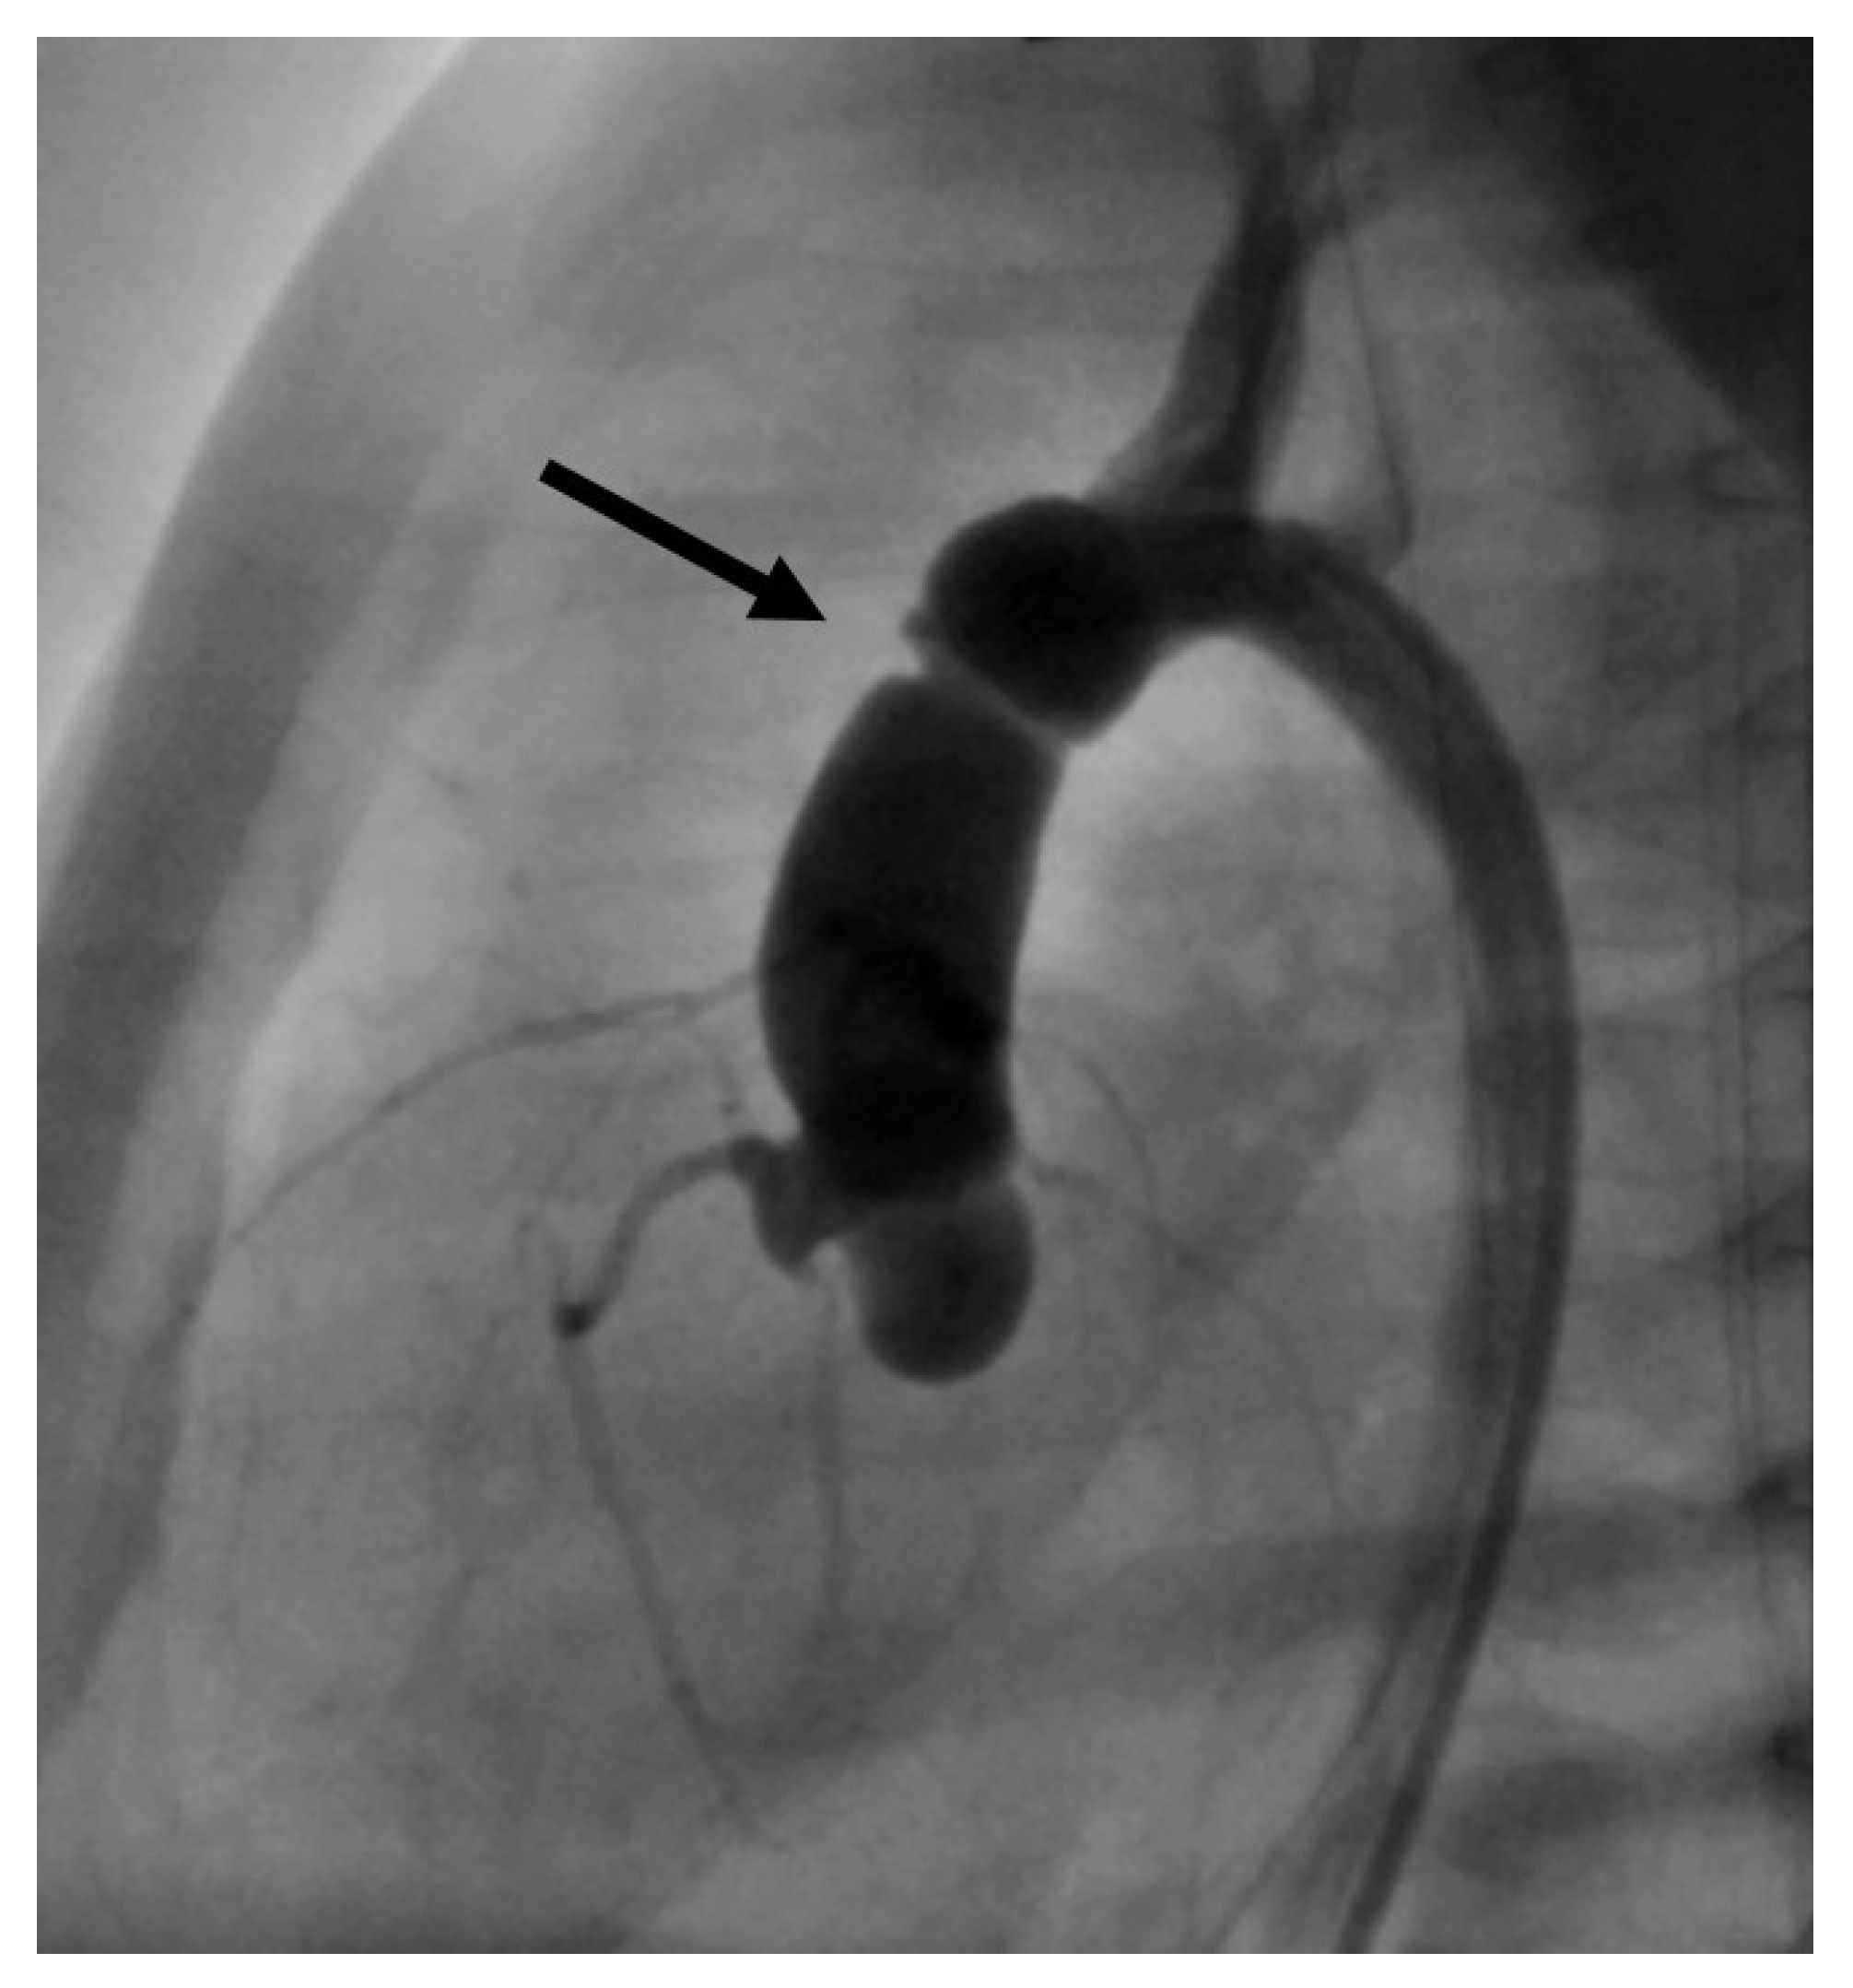

• In the same patient, an aortic wall injury resulting in a constriction of the intima following the second BAV occurred (Figure 8). However, this constriction was without significant stenosis, and was corrected at the time of necessary aortic valve repair.

Figure 8. Angiographical image, lateral view. Intimal lesion with consecutive constriction in the ascending aorta (arrow).